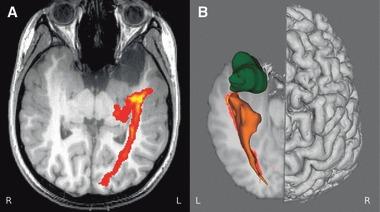

About one-third of patients with epilepsy are refractory to medical treatment and may be amenable to surgery. However, in patients with lesions on or near the presumed course of the optic radiation, the potential benefits of resection must be balanced against the risk of a visual field deficit. This study demonstrates the utility of diffusion tensor imaging (DTI) tractography in delineating the course of the optic radiation and its relationship to the epileptogenic lesion prior to epilepsy surgery.

Anatomic and DTI scans were acquired on 10 patients with medically refractory epilepsy undergoing presurgical evaluation at the National Hospital for Neurology and Neurosurgery. Five patients underwent surgery and repeat scans postoperatively. The optic radiation was delineated and visualized in relation to the lesions on anatomic images and in three-dimensional (3D) reconstructions. Preoperative and postoperative visual fields were acquired by Goldmann perimetry.

The entire optic radiation was reliably delineated bilaterally in all patients. The results provide helpful additional information in informing the patient of the risks of surgery and in planning the surgical procedure and approach. Postoperative imaging findings correlated with the visual field data.

The optic radiation shows significant anatomic variability, but can be reliably delineated by tractography. Because surgical disruption of the optic radiation has serious consequences for the patient, DTI tractography is a useful technique in this population. Future integration with real-time neuronavigation will minimize the risks of neurosurgery.